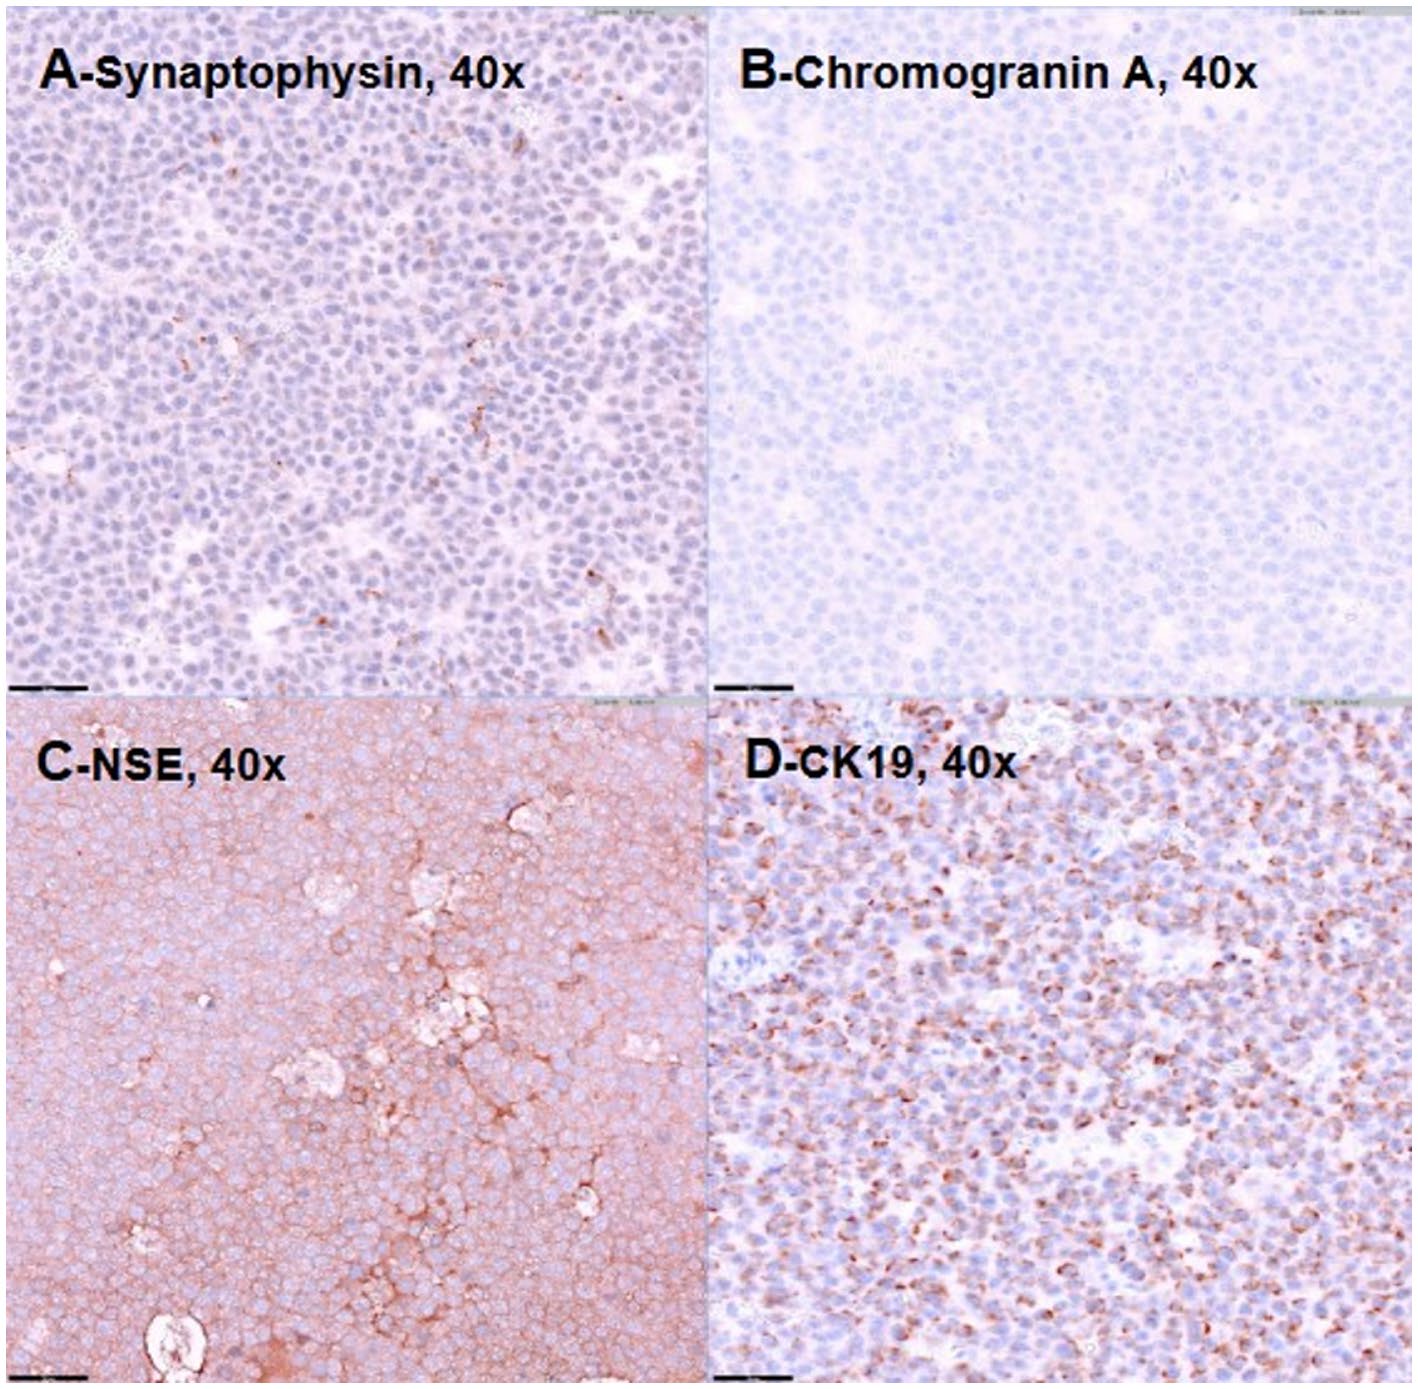

初步免疫组化结果显示,肿瘤细胞缺乏CD3和PAX5的表达,排除了淋巴瘤,同时也排除了肾母细胞瘤。鉴于肿瘤的解剖位置和组织形态学特征,副神经节瘤成为主要的鉴别诊断。神经元特异性烯醇化酶和突触素呈强阳性,嗜铬颗粒素A在10-20%的细胞中呈阳性,支持神经内分泌起源(下图A-C)。细胞角蛋白19在多达40%的肿瘤细胞中呈点状细胞质阳性(下图D),而波形蛋白呈弱阳性(5%)。神经丝蛋白和肌动蛋白的阴性染色有效排除了神经元和肌源性分化。最终,该肿块被诊断为腹膜后肾上腺外副神经节瘤。

↑ 代表性图像显示突触素(A)、嗜铬颗粒素A(B)、神经元特异性烯醇化酶(C)和细胞角蛋白19(D)的阳性免疫染色。